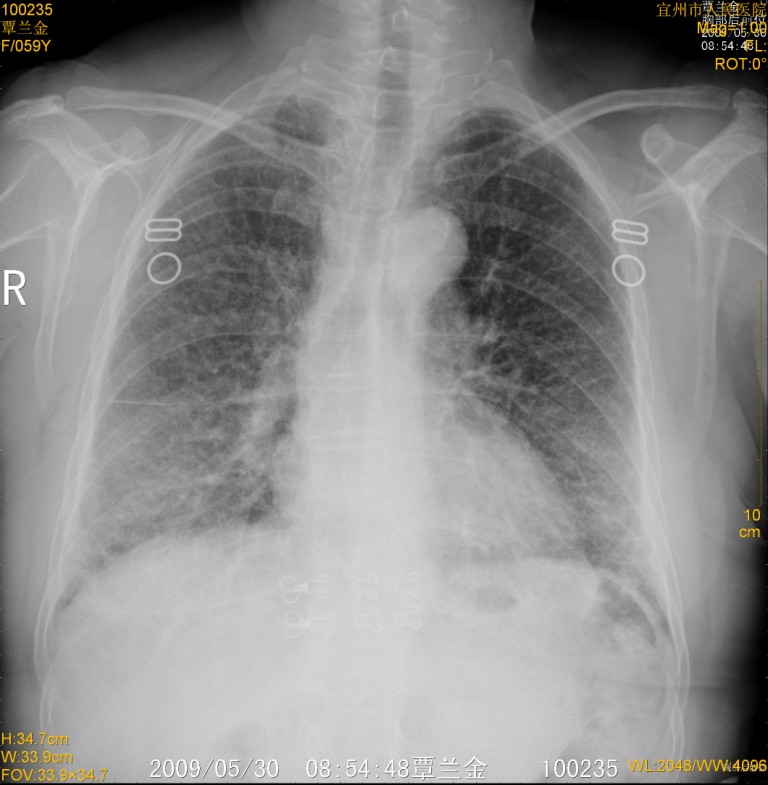

标题: CT20268:肺泡癌?间质性肺炎?

女,62岁,近二年经常咳嗽,近二个月,消瘦、乏力。

前面一张胸片是今天照的,后面一张胸片是去年9月份的。

弥漫性双肺间质纤维化。

两肺弥漫性间质性病变(间质性肺炎伴肺间质纤维化?)。